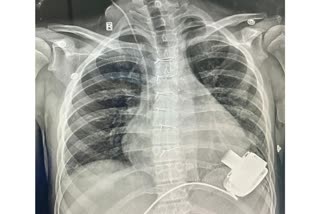

14ఏళ్ల ఉజ్బెకిస్థాన్ బాలుడికి గుండె వ్యాధి- 'మెకానికల్ హార్ట్' అమర్చిన భారతీయ వైద్యులు- కుర్రాడు ప్రాణాలు సేఫ్